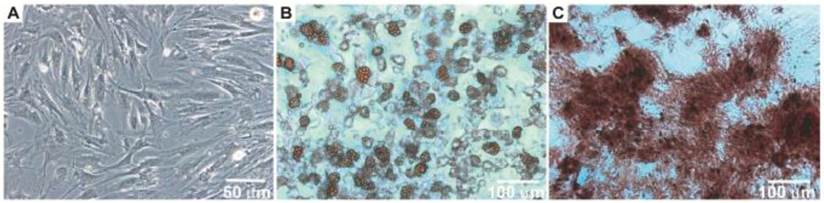

After the isolation and culture of the BM-MSCs, the cells grew to confluence and exhibited morphology similar to fibroblasts (Figure 1A). When the BM-MSCs were submitted to adipogenic stimulation, a shift in cell morphological features was observed from a primarily slender morphology to a spherical cell phenotype, and these cells were positively stained for lipid vacuoles by Oil Red-O (Figure 1B). In contrast, BM-MSC culture submitted to the osteogenic differentiation protocol resulted in an extracellular matrix positively stained for Alizarin Red (Figure 1C).

Figure 1

Morphology of bone marrow MSC (Panel A). Photomicrographs illustrating BM-MSC differentiation under adipogenic (Panel B) and osteogenic (Panel C) differentiation-inducing conditions.